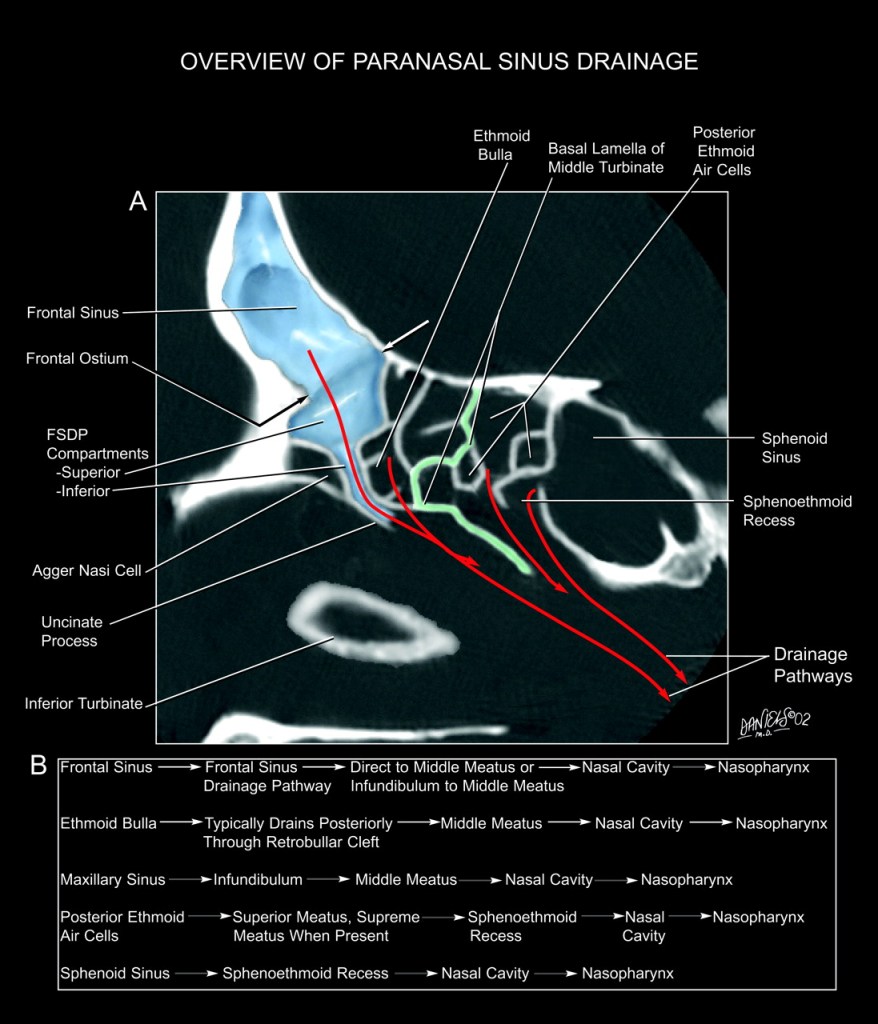

FSDP – frontal sinus drainage pathway – presence or absence and degree of penumatization of various cells and lamellas – ethmoid bulla, supra-bullar, fronto-bullar, supra-orbital, fronto-ethmoidal cells, and the Agger Nasi Cell.